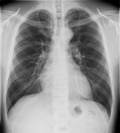

【概要】

一般撮影装置(GE Discovery XR650) 【装置の特徴】 ◆エネルギーサブトラクション法

◆トモシンセシス/デジタル断層撮影